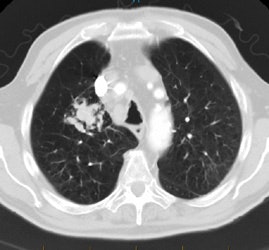

Rapidly enlarging lung cancer: The patient shown below was being followed for small lung nodules and prominent mediastinal lymph nodes. A chest CT in 2/2006 (left image) was stable to prior exams. A follow-up chest CT 10 months later (12/2006- right image) revealed a new, lung cancer in the right upper lobe. Extensive metastatic disease had already occurred. Such rapidly growing cancers may not be detected on screening CT exams. The small lung nodules (not shown) were again noted to be unchanged. |